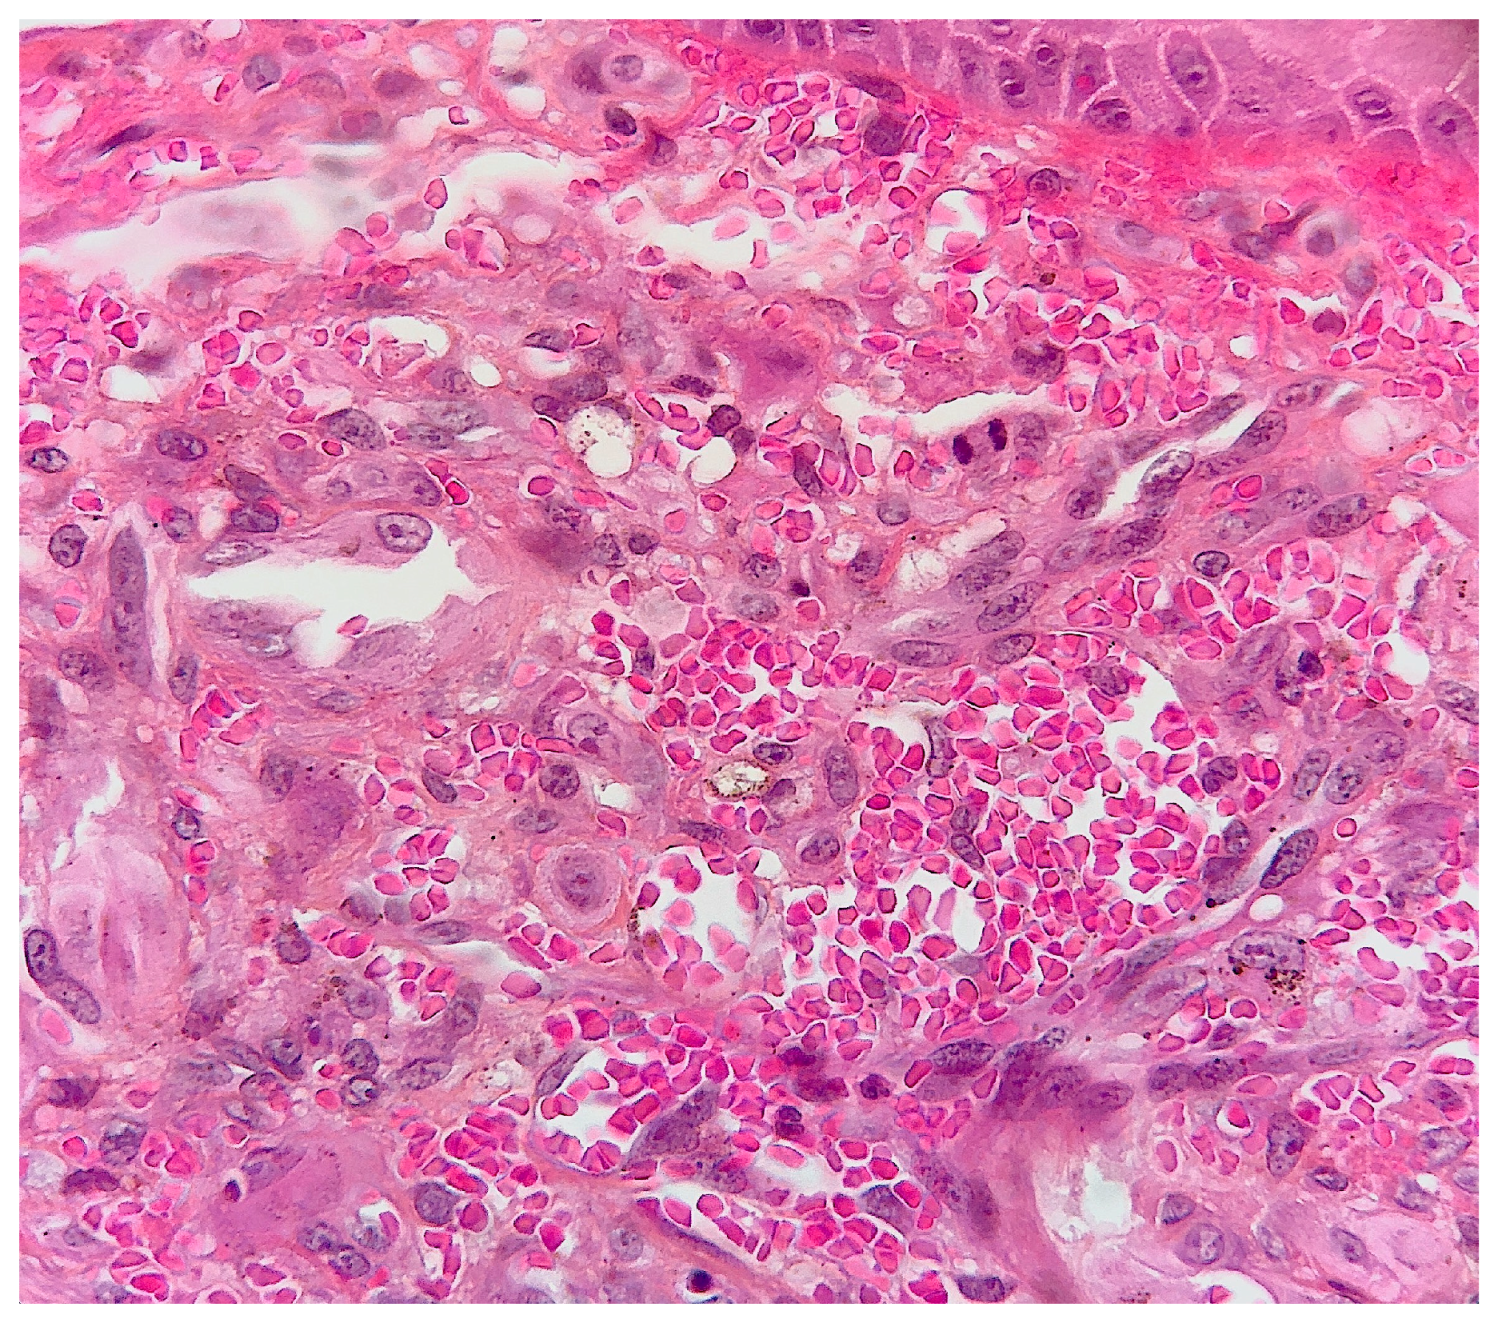

2. Case Report